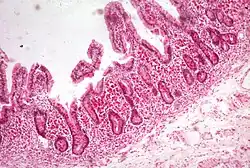

| Whipple's disease: Alcian blue with apparently eosin counterstain enlarged villus with many macrophages | |